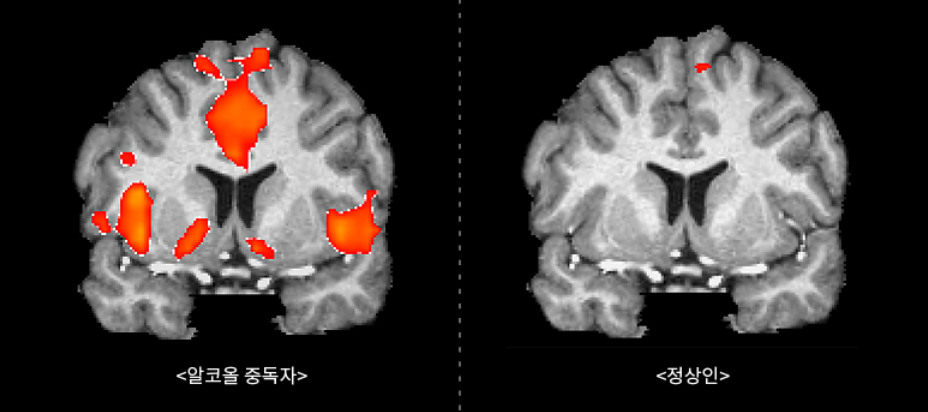

알콜중독자의 뇌는 일반인의 뇌와 다릅니다. 술 사진을 보여주었을 때 뇌 MRI사진의 차이입니다. 왼쪽 알콜중독자의 뇌는 술을 마시고 싶게 만드는 보상계의 위치가 빨갛게 활성화된 걸 알 수 있습니다. 그래서 알콜중독은 뇌구조의 변화가 원인인 진행성 뇌 질환이라고 합니다.